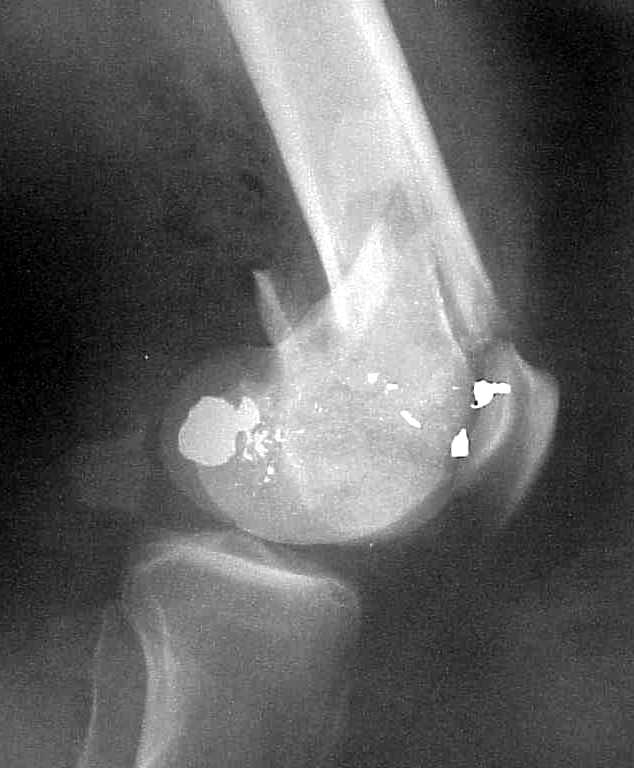

A CT and knee xrays would help identify lateral condyle comminution and/or a "hoffa fragment" of the posterior condyle. I am concerned that the lateral cortex is not sufficient to give purchase for a retrograde IMN. blocking screws could improve this as a possibility. A long blade or LISS if avaible would be my secondary choices. Good luck. Any chance you can get these cases transferred earlier when it

Lateral condyle looks too small for the blade, and the plate too short.

place one anterior to where IMN will go if anterior cortex if insufficient and AP screws on either side of the IMN out of the trochlea to provide some additional varus/valgus stability. I worry about the leg going into valgus w/the lack of lateral cortex.